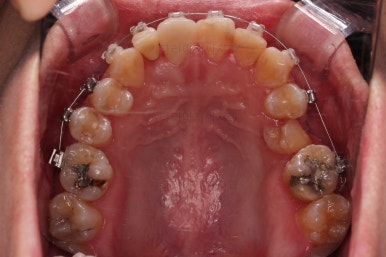

초진 시 입안의 모습입니다.

화살표는 결손 부위, 동그라기믄 유치잔존과 매복치아 부위입니다.

장치를 부착한 모습입니다.

이번 환자분은 자가결찰 세라믹(엠파워 클리어) 장치를 선택하셨고요.

잔존유치는 발치했고, 앞니 가짜치아는 벗겨내고 새로운 가짜치아를 와이어에 묶어주었습니다.